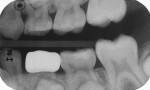

A 7-year-old girl presented with a fractured disto-occlusal, resin-modified glass-ionomer restoration on her primary mandibular left first molar that had been placed 30 months prior. The damage had permitted new caries to infect the distal third of the tooth (Figure 13). After local anesthesia was achieved and a rubber dam was placed, the carious tooth structure was debrided with a large round bur at slow speed, and the exposed dentin was covered with the resin-modified calcium silicate liner (Figure 14). Occlusal reduction was achieved in the same manner as in the previous case (Figure 15), and the axial reduction was cut to a shoulder preparation with the idea that the zirconia crown edge would seat onto the prepared margin (Figure 16). Two vertical grooves were included on the buccal aspect of the preparation to add to the surface area to improve luting cement adhesion. After the pink try-in crown established the proper size, the selected zirconia crown was filled with the luting cement and seated with finger pressure (Figure 17). The zirconia crown was observed 26 months after cementation (Figure 18 and Figure 19). At 33 months, the presence of advanced distal root resorption and eruption of the underlying premolar necessitated extraction of the crowned tooth (Figure 20 and Figure 21).